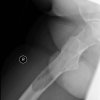

Hip Stress Fracture in a Runner | Cases

Published on May 4, 2020

19 female, triathlete c/o groin pain. started after a spike in training load over a 2 month period. 60km a week bike, 40-50 km running, 2-3 swims. Exam Antalgic gait Pain with FADIR and IR of hip NAD on X-ray. x-ray MRI MRI – Coronal Views What is the pathophysiology of a stress fracture?